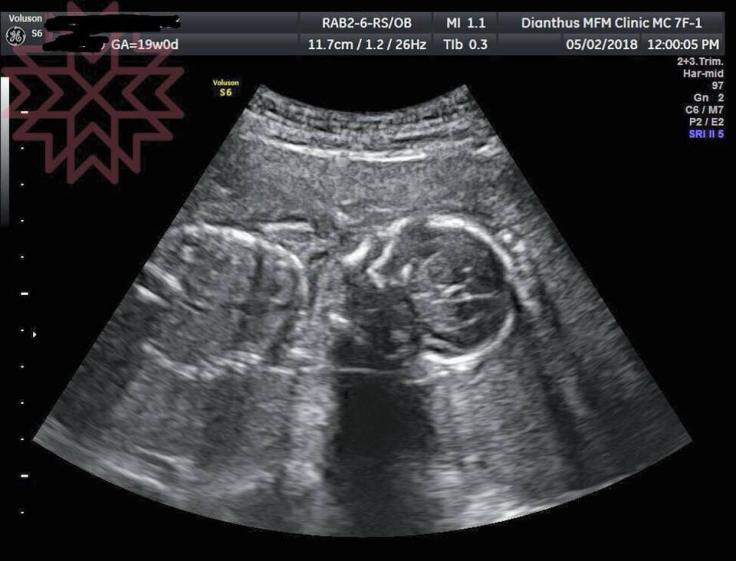

我請她上診療台用超音波評估

只是

探頭一放下去

很慘

就是現在看到的這張超音波照片

完全沒有羊水

上面記錄很清楚

2018年5月2日